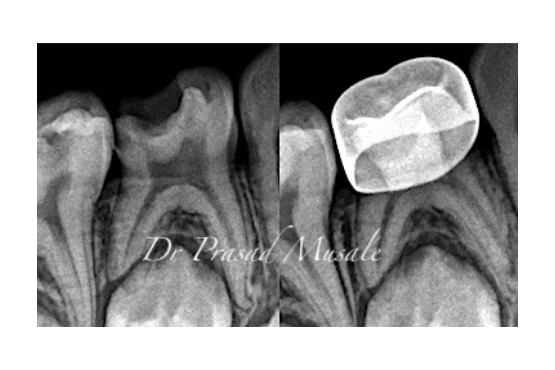

When the decay in your child’s tooth is deep but limited to the top of the pulp, we remove only the infected pulp leaving the healthy nerve intact, place a medicament and restore the tooth